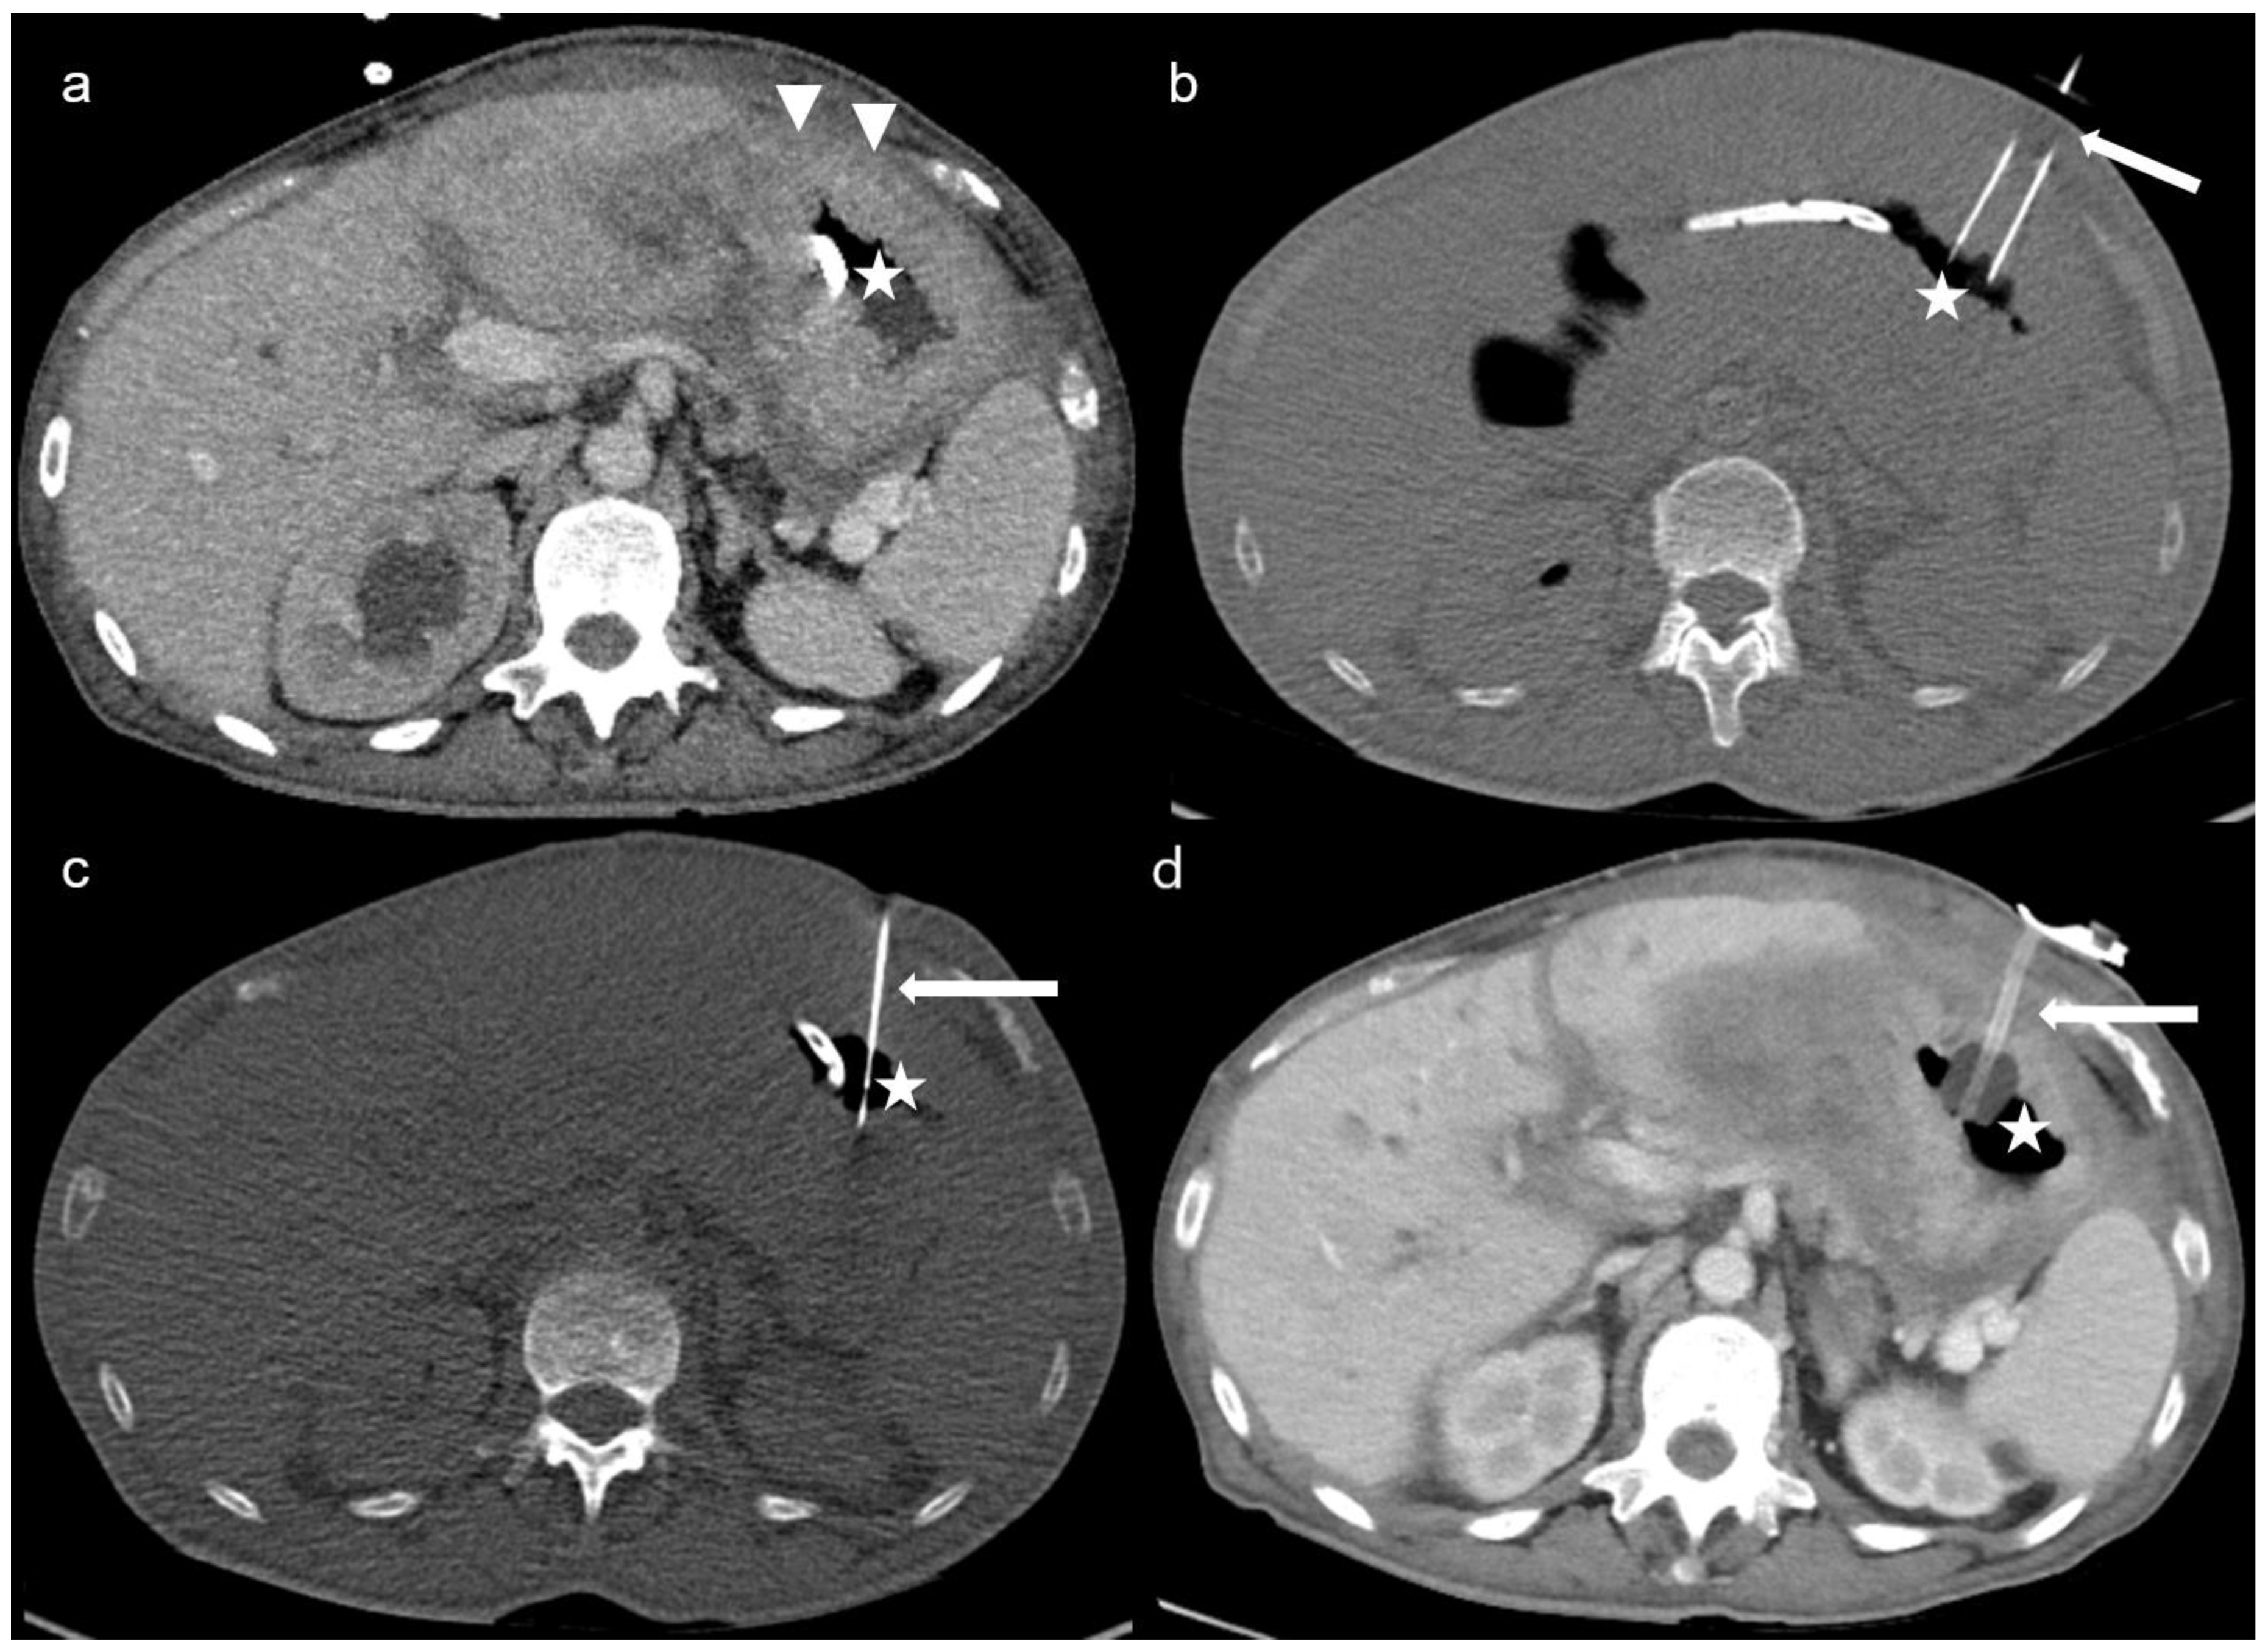

The technique of CT-PG was described in detail in a previous study of our institution, including all CT-guided gastrostomies with nutritional or decompressive purposes [15]. CT-PG was applied by the Seldinger technique under local anaesthesia with 1% lidocaine. In all patients, preprocedural sequential enhanced CT slices were acquired to demonstrate the anatomy, and CT-fluoroscopy was utilised for guidance. A gastropexy device was used to puncture the anterior gastric wall and to place the gastropexy sutures (Freka Pexact FR15; Fresenius Kabi, Bad Homburg, Germany). Figure 1 demonstrates the steps of the CT-PG in a case of peritoneal carcinomatosis, in whom endoscopic gastrostomy was not feasible due to inadequate transillumination.

Figure 1. Multiple sequential axial-enhanced CT and unenhanced CT-fluoroscopy images: (a) triangles show thickened peritoneal surfaces due to carcinomatosis, which hinders diaphanoscopy at the endoscopic approach. The nasogastric tube is used to insufflate the stomach (star); (b) the gastropexy device (arrow) passes through the abdominal wall and punctions the anterior gastric wall. Gastropexy sutures are applied 2 cm apart to fasten the stomach to the anterior abdominal wall; (c) an 18G access needle (arrow) is inserted in the air-filled stomach (star), followed by the introduction of a 0.035″ Amplatz super stiff wire (Boston Scientific, Marlborough, MA, USA) and the insertion of a 16F peel-away sheath (Cook Medical); (d) a 15F gastric tube (arrow) is placed in the gastric cavity (star) with an inflated balloon (Freka Pexact CH/FR 15).